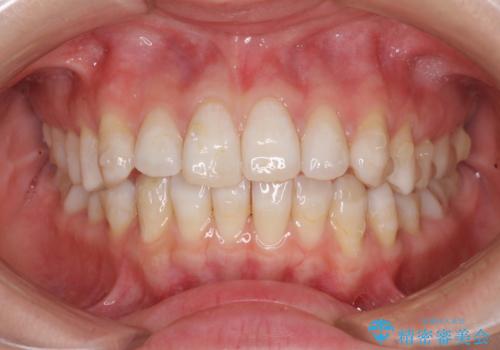

話しにくいオープンバイト インビザラインによる矯正治療

- 前歯の上下スペースによる話しにくさを気にして来院された患者様です。

インビザラインにより上下の前歯の隙間を閉じていくこととしました。

上下の奥歯を圧下させるようにすることで、前歯を接触させるように計画しました。

隙間に舌が入り込むことが話しにくさに繋がっていたため、舌の筋肉のトレーニングも並行して行い、話しにくさの改善と後戻りの抑制を図りました。